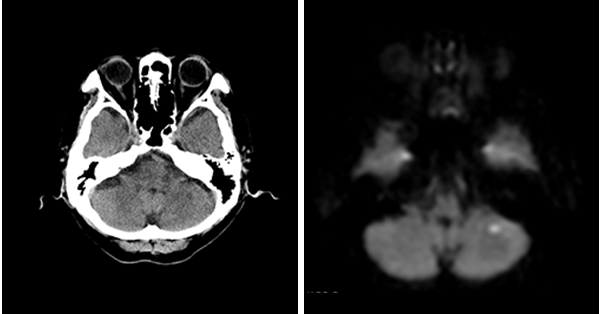

臨床画像例

中山氏 IPVは被ばく低減に役立っています。

当院では、体幹部は平均的にガイドライン*2比で50%近く低被ばくの条件で撮影していますが、読影の先生にも問題なく診断して頂いています。低被ばくに撮影することは、患者さんのメリットに繋がります。当院では、さらに患者さんに安心していただくため、被ばく線量を集計して患者さん向けの説明ツールを作っています。